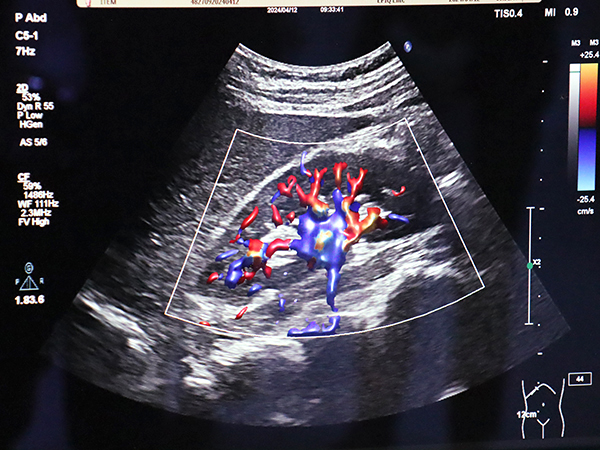

超音波診断装置は,「EPIQ」「Affiniti」の最新ソフトウエア「VM10」と超高周波マイクロリニア「mL26-8トランスジューサ」を中心に展示した。VM10には新たに自動画像調整ツール「AutoSCAN Assistant」が搭載され,輝度やフォーカス位置を自動調整することで検査者に依存しない一貫したイメージクオリティを提供する。また,血流に立体感を与える血流イメージ「Flow Viewer」は,血管をより鮮明に描出し視認性を向上させる。mL26-8トランスジューサは,8~26MHzの周波数をカバーし,非常に浅い領域から乳腺,表在血管,整形,眼球など幅広い領域に対応する。

超音波診断装置の最新ソフトウエア「VM10」に搭載された血流イメージ「Flow Viewer」